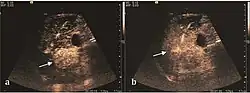

HCC appearance on 2D ultrasound is that of a solid tumor, with imprecise delineation, with heterogeneous structure, uni- or multilocular (encephaloid form). An "infiltrative" type is also described which is difficult to discriminate from liver nodular reconstruction in cirrhosis. Typically HCC invades liver vessels, primarily the portal veins but also the hepatic veins . Doppler examination detects a high speed arterial flow and low impedance index (correlated with described changes in tumor angiogenesis). The spatial distribution of the vessels is irregular, disordered. CEUS examination shows hyperenhancement of the lesion during the arterial phase. During the portal venous phase there is a specific "wash out" of ultrasound contrast agent (UCA) and the tumor appears hypoechoic during the late phase. Poorly differentiated tumors may have a stronger wash out leading to an isoechoic appearance to the liver parenchyma during portal venous phase. This appearance was found in approx. 30% of cases. The described changes have diagnostic value in liver nodules larger than 2 cm.